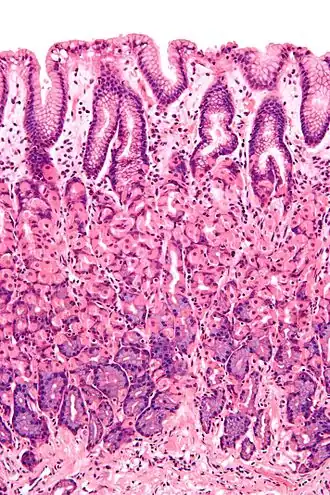

![]() Microscopic section of gastric mucosa. Foveolar cells can be seen at top of the image lining the surface and pits | |

Foveolar cells or surface mucous cells are mucus-producing cells which cover the inside of the stomach, protecting it from the corrosive nature of gastric acid.[1][a] These cells line the gastric mucosa and the gastric pits. Mucous neck cells are found in the necks of the gastric glands. The mucus-secreting cells of the stomach can be distinguished histologically from the intestinal goblet cells, another type of mucus-secreting cell.

The gastric mucosa that lines the inner wall of the stomach has a set of microscopic features called gastric glands which, depending on the location within the stomach, secrete different substances into the lumen of the organ. The openings of these glands into the stomach are called gastric pits which foveolar cells line in order to provide a protective alkaline secretion against the corrosive gastric acid.[2]: 256

Foveolar cells line the surface of the stomach and the gastric pits. They constitute a simple columnar epithelium, as they form a single layer of cells and are taller than their width. Other mucus-secreting cells are the mucous neck cells in the necks of the gastric glands.[2]: 257

Surface mucous cells have large quantities of mucin granules in their apical (top) surface and project short microvilli into the lumen of the stomach.[2]: 257 Mucins are large glycoproteins that give the mucus its gel-like properties.[3] As mucins are lost during routine histology preparation, they stain pale, but if preserved correctly the cells stain strongly with special techniques like PAS or toluidine blue, the last representing the anionic nature of foveolar cell secretions. Below the mucin granules, surface mucous cells have a Golgi apparatus, the nucleus, and small amounts of rough endoplasmic reticulum.[4]: 577 Mucous neck cells are located within gastric glands. These are shorter than their surface counterpart and contain lesser quantities of mucin granules in their apical surface.[4]: 578